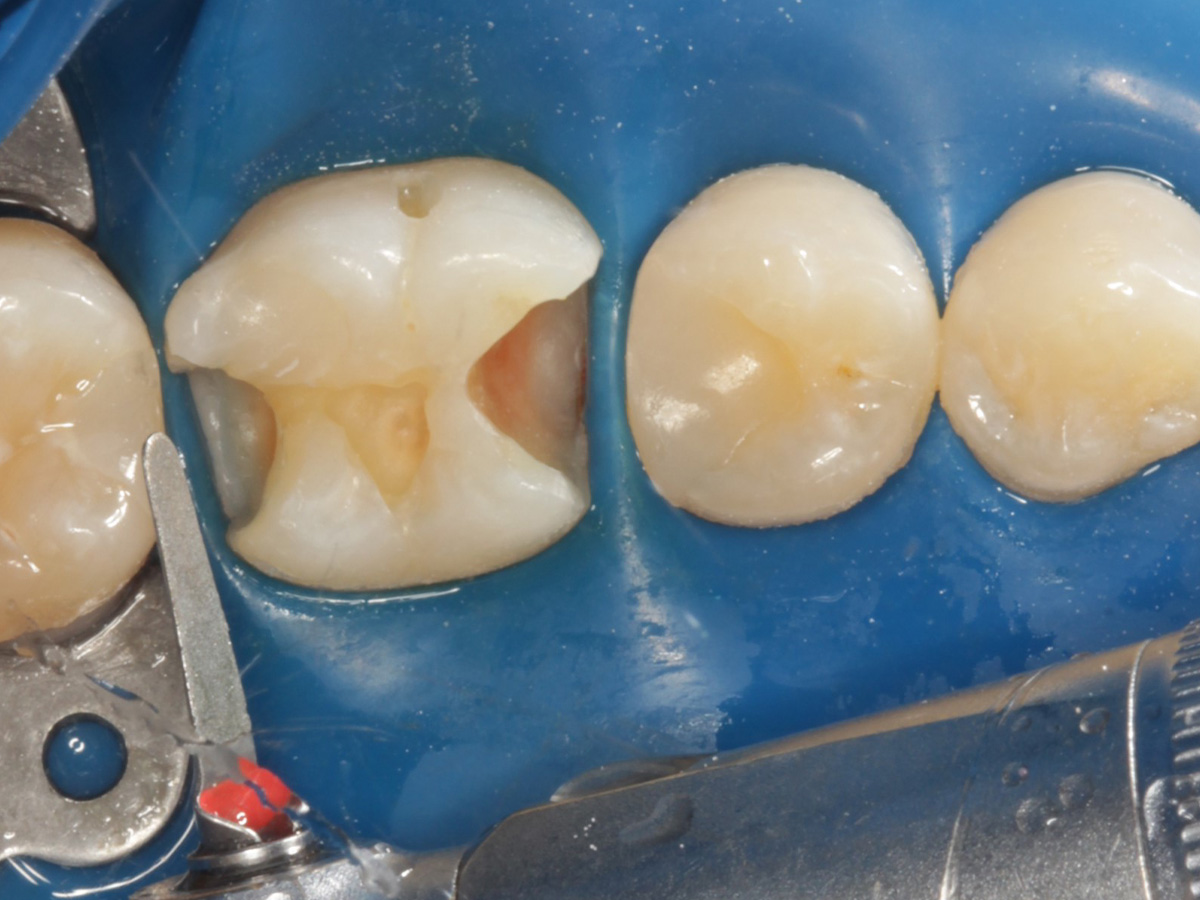

Distale Kavität gefüllt, Matrize distal entfernt und Bioclear Twin Ring Universal nach mesial versetzt, mesial vorher: Bioclear Diamond Wedge Large

Abbildung 19

Kavitäten gefüllt (Injektion Moulding: Flowkomposit, erwärmtes Seitenzahnkomposit aus Karpule)

Abbildung 20